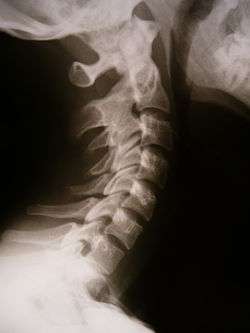

![]() X-ray showing synostosis in the cervical spine | |

Synostosis (plural: synostoses) is fusion of two bones. It can be normal in puberty, fusion of the epiphysis, or abnormal. When synostosis is abnormal it is a type of dysostosis.